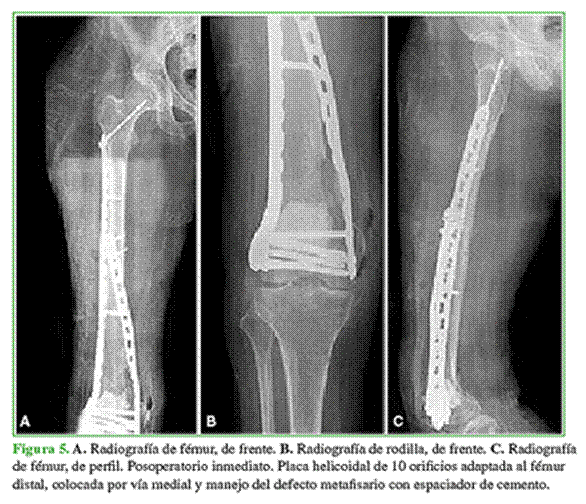

En todos los pacientes, se observó la consolidación radiográfica a los seis meses de la cirugía definitiva. Dos pacientes de la muestra tenían, en el momento de la osteosíntesis, defectos metafisarios que fueron resueltos con espaciadores de cemento y antibiótico, por lo que requirieron una nueva intervención con la colocación de injerto de banco. En estos casos, la carga se retrasó seis semanas, momento en el cual se realizó el segundo tiempo quirúrgico que consistió en el retiro del espaciador y el relleno del defecto con injerto óseo cadavérico. Nuevamente, se retrasó la carga seis semanas, y se logró la consolidación en ambos casos. En el resto de los pacientes, se inició un protocolo de carga progresiva que consistió en carga parcial por tres semanas y luego carga completa. Ninguno tuvo una lesión vasculonerviosa asociada (Figuras 3-6).

El puntaje promedio de dolor posoperatorio luego de la consolidación de la fractura fue 3. El paciente con cuadriplejia no fue evaluado en este aspecto (Tabla 2). El seguimiento radiográfico se realizó en el posoperatorio inmediato, a las 3 y 6 semanas, y a los 3, 6, 12, 18 y 24 meses. En la Tabla 3, se describen los resultados funcionales según el puntaje KOOS.6,7 La mediana de seguimiento fue de 24 meses (rango 6-36).

En un estudio biomecánico, Sezek y cols. compararon las placas rectas con las placas helicoidales colocadas por vía medial. Sostienen que la osteosíntesis recta convencional induce una protección indebida por tensión del hueso fracturado y puede causar algunos problemas de debilitamiento y aflojamiento del segmento. Otra desventaja es la falta de capacidad de torsión, lo que dificulta la colocación de la placa y puede determinar un grado de mala rotación de la fractura. Estos autores llegaron a la conclusión de que las placas helicoidales tienen mayor estabilidad ante la carga axial y las fuerzas torsionales en comparación con las placas rectas convencionales; sin embargo, las placas rectas tuvieron más resistencia a las fuerzas de flexión.8 Esto último probablemente se deba a que las placas helicoidales, al estar grifadas, son más débiles en los puntos donde se aplicó la fuerza.9 En nuestra serie, dos pacientes presentaron defectos metafisarios severos de fémur distal, por lo que el uso de doble osteosíntesis aumentó la rigidez del sistema, y les permitió a los pacientes la marcha con carga parcial inmediata luego de la cirugía definitiva y la carga completa a las seis semanas.